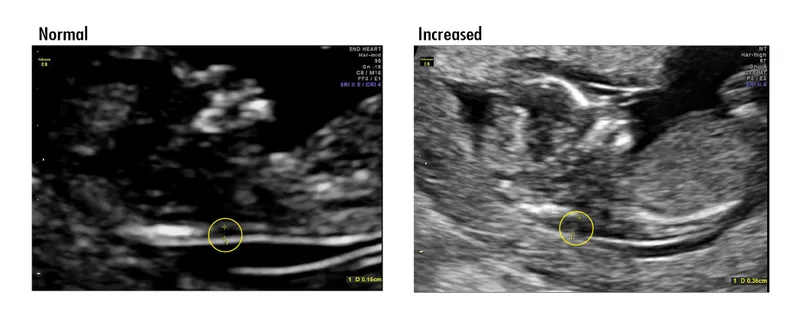

⭐ Nuchal Translucency (NT) >3.5mm is a significant marker for aneuploidy (e.g., Trisomy 21) and fetal cardiac anomalies.

- USG: ↑ Nuchal Translucency (NT)

- 1st Tri: NT, nasal bone.